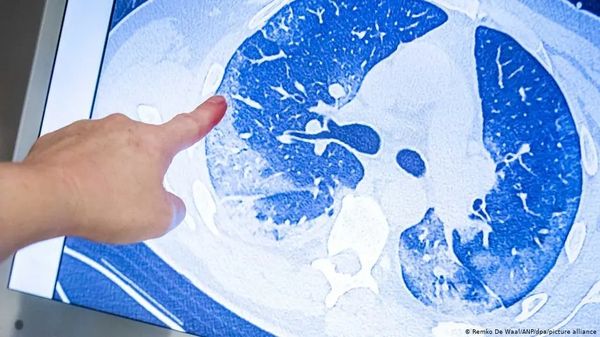

每次随访时,患者都接受了详细的面谈、体检和6分钟的步行测试,也回答了各种问卷,反映他们呼吸困难的情况、生活质量、出院后就医情况等等。研究人员在6个月时随机抽样病人做了肺功能检查和胸部CT,根据需要12个月时又有复查。